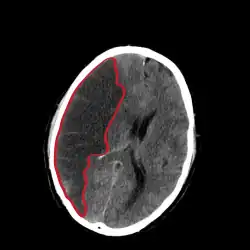

CT scan slice of the brain showing a right-hemispheric cerebral infarct (left side of image).